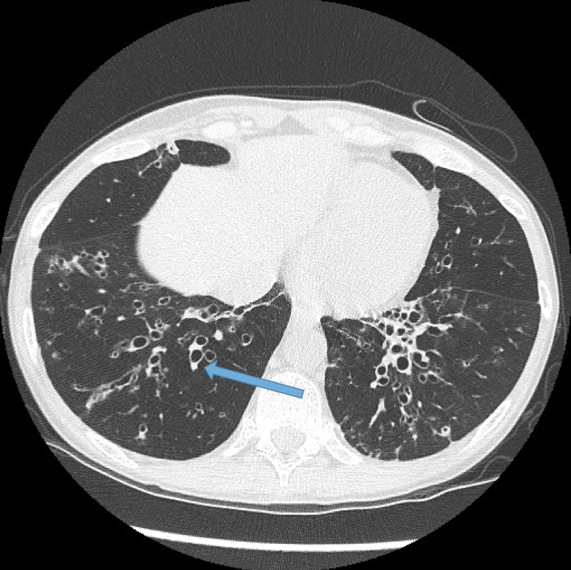

The gold standard diagnostic imaging for bronchiectasis is a high-resolution CT scan (HRCT), what findings would there be?

• ‘signet ring sign’

11

Q

What is this sign on the CT scan and what does it indicate?

signet ring sign and tram line appearance indicates bronchiectasis --> indicates bronchial dilation